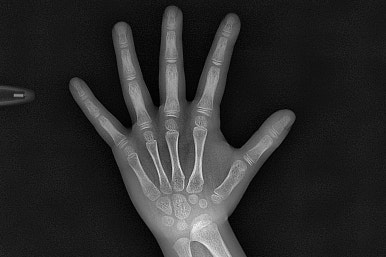

골연령(성장판 검사)과 골격 분석

성장판 검사를 통해 골연령을 예측하는데요.

저희 부산프리올소 키다리아저씨치과는 좀 더 세부적인 나이까지 알 수 있도록 Greulich-Pyle법을 이용해서 나이를 추정하고요. 치료가 가능한 적절한 나이에 치료를 들어갑니다.

또한 골격 분석을 하여 골격이 문제인지, 골격의 문제라도 단순히 앞뒤로의 문제인지 폭이나 높이의 문제는 없는지 등등 포괄적으로 분석합니다.